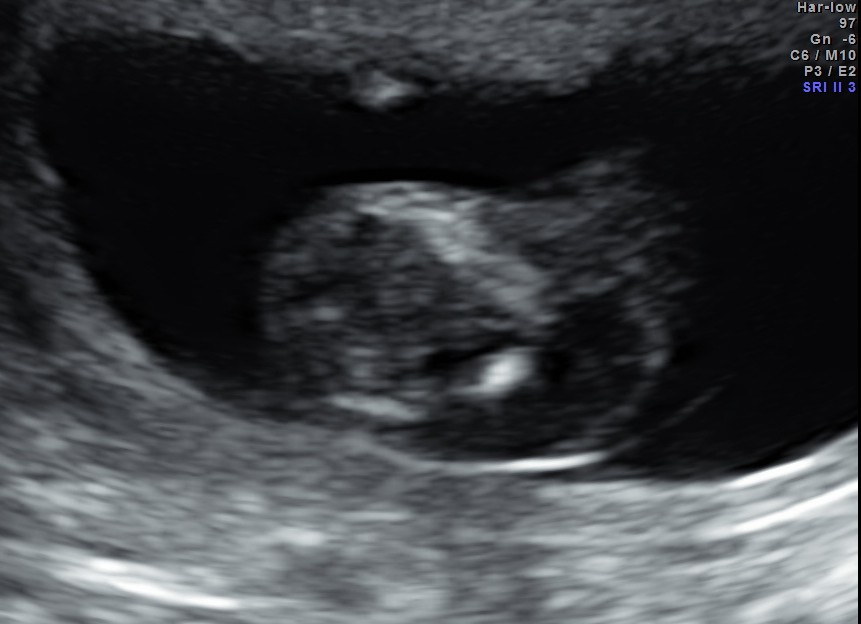

This 23 year old primi gravida, with no history of consanguinity was referred for 2nd opinion for evaluation of cystic swelling of the neck in the first trimester.

The following are the 2 d pictures.

The diagnosis offered was cystic hygroma .